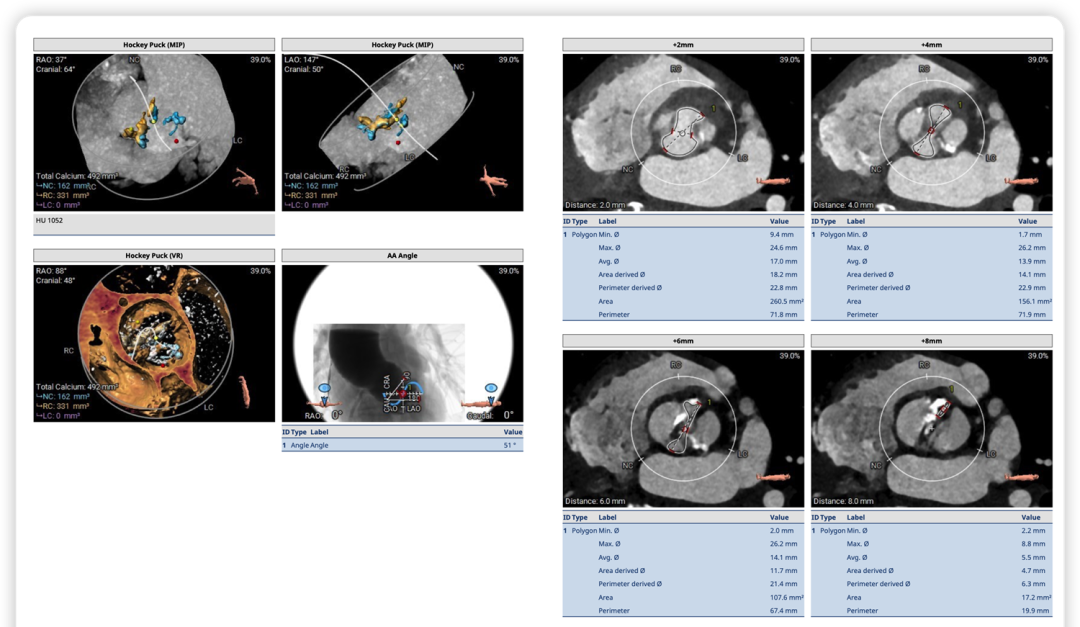

术前CT